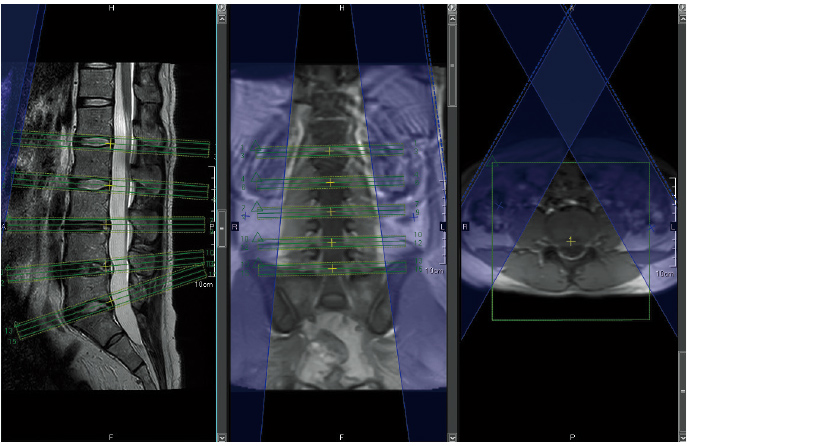

AutoPose*1

Skanogram işlevi, bilgilerin operatörler için bölgelerin kesit alanlarında hızlı bir şekilde görüntülenmesini sağlar.